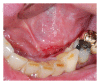

Infections are increasingly considered as potential trigger for carcinogenesis apart from risk factors like alcohol and tobacco. The discussion about human papilloma virus (HPV) in oral squamous cell carcinoma (OSCC) points at a general role of infection for the development of oral carcinomas. Furthermore, first studies describe a correlation between chronic periodontitis and OSCC, thus, characterizing chronic inflammation as being a possible trigger for OSCC. In front of this background, we present four well-documented clinical cases. All patients showed a significant anatomical relation between OSCC and clinical signs of chronic periodontitis. The interindividual differences of the clinical findings lead to different theoretical concepts: two with coincidental appearance of OSCC and chronic periodontitis and two with possible de novo development of OSCC triggered by chronic inflammation. We conclude that the activation of different inflammatory cascades by chronic periodontitis negatively affects mucosa and bone. Furthermore, the inflammatory response has the potential to activate carcinogenesis. Apart from a mere coincidental occurrence, two out of four patients give first clinical hints for a model wherein chronic periodontitis represents a potential risk factor for the development of OSCC.